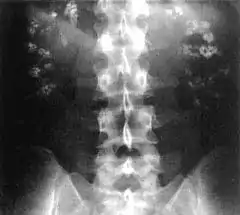

![]() Radiografía en la que se aprecia la existencia de depósitos de calcio en ambos riñones (nefrocalcinosis). | ||

En medicina, se denomina nefrocalcinosis a la existencia de depósitos de calcio en el parénquima del riñón que puedan detectarse mediante pruebas de imagen como radiografía o ecografía. No constituye una enfermedad en sí misma, sino un síntoma que puede deberse a diferentes causas, entre ellas el hiperparatiroidismo, la intoxicación por vitamina D y la acidosis tubular renal tipo I. Suele asociarse a elevación del nivel de calcio en sangre (hipercalcemia) y exceso de eliminación de calcio a través de la orina (hipercalciuria). Se detecta mediante pruebas de imagen, en la ecografía, por ejemplo, se aprecian los depósitos de sales de calcio localizados en diferentes partes del riñón como la médula renal y la papila renal.